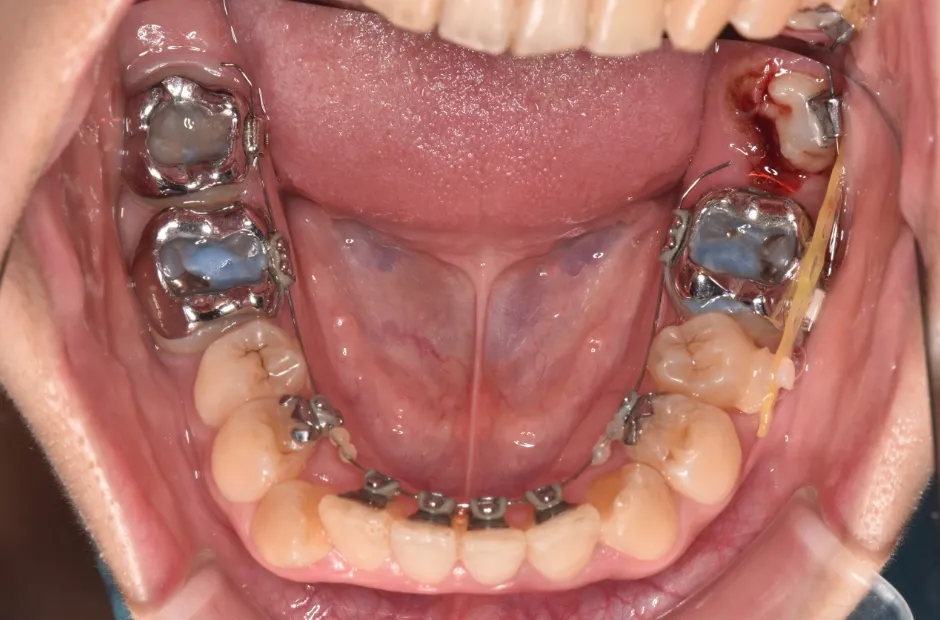

| 診断名・主訴 | 開咬 |

|---|---|

| 年齢・性別 | 23歳・女性 |

| 治療期間・回数 | 1年 12回 |

| 治療に用いた主な装置 | クワドヘリックス(QH)+タングガード → ロール付きリンガルアーチ |

| 抜歯部位 | 左右下8番 |

| 治療費 | 70万円(税抜) |

| リスク・副作用 | 装置による違和感・疼痛・歯肉退縮・歯根吸収・虫歯のリスクなど |

治療前